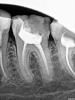

Magdalena Опубликовано 2 декабря, 2012 Поделиться Опубликовано 2 декабря, 2012 (изменено) Пациентка 28 л, обратилась с жалобой на скол стенки зуба 3.6. Объективно: зуб под обширной пломбой с нарушением прилегания, кариозная полость на дистальной поверхности. Перкуссия, пальпация безболезненныНа снимке увидела ступень, сразу предупредила о ее наличии, а также, что в процессе лечения может быть перфорация. В 1ое посещение прошла дистальный щечный и медиальный язычный, ступень в медиальном щечном не прошла, постоянно втыкалась в нее. Работала не в своем кабинете, скопа под рукой не былоОтправила на КТ, давайте, говорю, посмотрим, есть там дальше ход или нет (хотя, конечно, уверена была, что есть). На КТ четко видно, что медиальные проходимы до апекса. Во 2ое посещение, опять воткнулась в ступень, глянула в скоп и увидела кусок гутты в просвете канала, хотя на снимке с инструментами материала в канале не видно. Гутту убрала, канал прошла.Обработка 3,25% р-р гипохлорита, УЗ, в конце обработки - дист. вода и 17% ЭДТА, mtwo до 25\06, доработка ручными в медиальных до № 30, в дистальном № 45, все остальные пролетали. Смущает, что такой широкий дистальный, не расширяла специально, mtwo только по стенкам поскребла, все остальное УЗ. 2ого дистального точно нет, не в скоп, ни по КТ. Изменено 2 декабря, 2012 пользователем Magdalena 4 Ссылка на комментарий